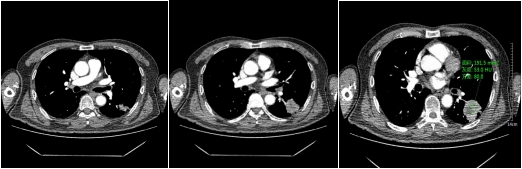

动脉期

静脉期

不同性质的结节,因为内部组织成份不同所以强化的方式不同,结节的供血方式也有不同,所以不同性质的肺结节,强化的方式也是不同。比如:急性期炎性肺结节因为组织成份多为肉芽组织,血管丰富,所以增强后明显强化,往往比平扫示强化程度高60HU以上;慢性期炎性肺结节,其主要成份示纤维组织,强化比较轻微,CT值较平扫多高20HU。

恶性实性结节,病变内含有肿瘤组织血管,强化程度不如急性炎性结节,增强CT扫描多升高20-60HU之间。

对于实性结节、亚实性磨玻璃结节具有以上恶性征象,就需要进一步CT增强扫描。增强CT的意义在于观察结节与周围血管的关系,结节本身有没有血供及血供的程度。因此,需要专业医师根据结节强化的方式、程度,结节本身的形态特征,与周围组织的关系,全面评估结节的性质,判断结节良恶性,为患者的治疗制定下一步措施。